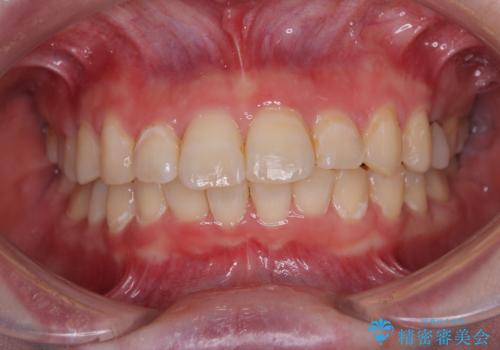

上下前歯の距離が大きかったため、上下の歯が接触するまでに時間がかかりました。

それでも目安である2年半で終えることができ、患者様には大変満足していただけました。